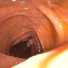

Optical colonoscopy (OC), the most prevalent colon cancer screening tool, has a high miss rate due to a number of factors, including the geometry of the colon (haustral fold and sharp bends occlusions), endoscopist inexperience or fatigue, endoscope field of view, etc. We present a framework to visualize the missed regions per-frame during the colonoscopy, and provides a workable clinical solution. Specifically, we make use of 3D reconstructed virtual colonoscopy (VC) data and the insight that VC and OC share the same underlying geometry but differ in color, texture and specular reflections, embedded in the OC domain. A lossy unpaired image-to-image translation model is introduced with enforced shared latent space for OC and VC. This shared latent space captures the geometric information while deferring the color, texture, and specular information creation to additional Gaussian noise input. This additional noise input can be utilized to generate one-to-many mappings from VC to OC and OC to OC. The code, data and trained models will be released via our Computational Endoscopy Platform at https://github.com/nadeemlab/CEP.

More than 15 million colonoscopies are performed in the US every year [1, 2]. During these procedures, 22-28% of polyps and 20-24% adenomas are missed [3]. There are no commercial or automated tools available to assist endoscopists in gauging the amount of colon surface missed during optical colonoscopy (OC) procedures. The main culprit in substandard coverage during colonoscopy are the sharp bends and haustral folds, as depicted in Figure 1a. Even though the endoscope tip can be flexed to look behind folds and sharp bends, beginner or tired endoscopists might not use this option wisely and may have a high miss rate. This high miss rate can be reduced if endoscopists have a visualization tool to identify and investigate areas occluded by haustral folds.

In this paper, we present a deep learning model for realtime visualization of missed colon surfaces directly on the colonoscopy video frames without doing any prior offline 3D reconstruction using contiguous sets of frames. Specifically, we make use of prior 3D reconstructed virtual colonoscopy (VC) [7, 8] data, created from a computed tomography (CT) scan, to produce training data for missing surface visualization (Figure 1b–d). This is used in conjunction with OC data for the same patient to drive an unpaired image-to-image translation with a modified lossy CycleGAN [4] and a new enforced shared OC and VC latent space representation. The lossy CycleGAN [4] by itself overfits due to the sparse training data for the missing surface task (most OC frames have no or few missing surface green pixels as opposed to the dense depth maps for which the lossy CycleGAN was originally proposed) and can easily hallucinate structures which do not exist, as shown in Figure 1. Adding a shared latent space forces the network to preserve structures (and avoid hallucination) when translating between domains. With added Gaussian noise, we also show that the same framework with shared latent space representations can be used to generate realistic one-to-many mappings from VC to OC and OC to OC for augmenting OC datasets in computer-aided detection and classification pipelines.

In order to create training data for per-frame missing surface visualization, the opacity of the 3D colon mesh is lowered such that the more opaque regions indicate the missed surfaces, which are colored green in Figure 1c. The per-frame missing surface data is generated through Blender and example videos are provided111Supplementary Video: https://youtu.be/x1-wwCiYeC0. Figure 1 shows a typical colon anatomy along with the haustral folds and the pictorial representation of a missed surface for a certain endoscope camera position. To aid the model with the image-to-image domain translation task, we added the missing surface information in green channel on top of the VC rendering of the colon (Figure 1d).